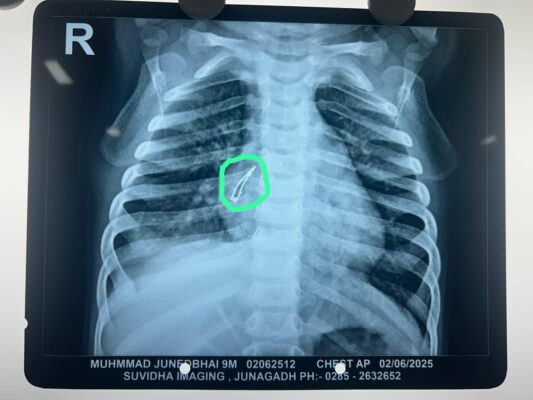

છેલ્લા ઓગણીસ દિવસથી આમ થી તેમ અમારા બાળકની તકલીફની સારવાર માટે દોડી રહ્યા હતા, પણ છેલ્લે સાચી સારવાર સિવિલ હોસ્પિટલ, અમદાવાદમાં જ મળી આ શબ્દો છે બાળકના પિતા જુનેદભાઇના. કારપેન્ટરનુ કામ કરતા મંગરોળ, જુનાગઢ ના રહેવાસી એવા જુનેદ યુસુફ અને તબસ્સુમબેનના લાડકવાયા એવા 9 માસના નાનકડા પુત્ર મોહમ્મદને છેલ્લા ૧૫ દિવસથી ઉધરસ આવતી હતી. જુનાગઢ માં બાળરોગ તજજ્ઞને બતાવતા તેનો છાતીનો એક્સ-રે કરાવતા તેમાં શ્વસનનળીમાં કાંઈક હોવાની માલુમ પડ્યુ હતુ. જુનેદ ભાઇને રાજકોટની ખાનગી હોસ્પિટલ દ્વારા વધુ તપાસની ભલામણ કરવામાં આવી પણ તેનો ખર્ચ તેમને પોષાય તેમ ન હોવાથી તેમના માટે સિવિલ હોસ્પિટલ અમદાવાદ આશાની કિરણ બની જ્યાં સારવાર અર્થે બાળક ને લઇ આવતા તારીખ ૩ જૂન, ૨૦૨૫ ના રોજ બાળકને પીડીયાટ્રીક સર્જરી વિભાગ માં તાત્કાલિક દાખલ કરવામાં આવ્યુ.

સિવિલ હોસ્પિટલ, અમદાવાદના પીડિયાટ્રિક સર્જરી વિભાગના વડા ડૉ. રાકેશ જોશી તેમજ એનેસ્થેસિયા વિભાગના પ્રોફેસર ડૉ. નિલેશ અને તેમની ટીમ દ્વારા બાળકની બ્રોન્કોસ્કોપી કરી જમણી તરફની મુખ્ય શ્વાસનળીમાંથી એક એલઇડી બલ્બ સફળતાપુર્વક બહાર કાઢવામા આવ્યો. ઓપરેશન પછી બાળકની તબીયત ઝડપથી સુધરી રહી છે અને કોઇપણ બીજી તકલીફ વગર બાળક હવે સ્વસ્થ છે. જેથી ટુંક સમય માં તેને હોસ્પિટલમાંથી રજા આપવામાં આવશે તેમ ડોક્ટરોએ જણાવ્યુ હતુ.